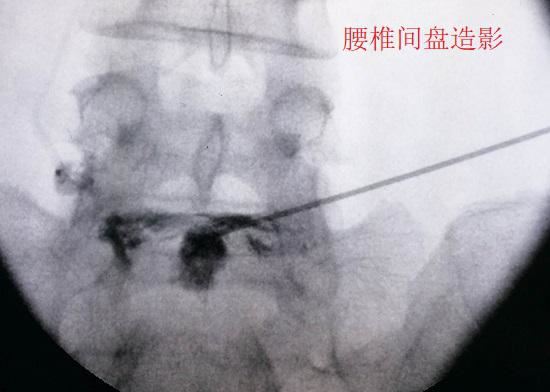

腰椎间盘内部虽然没有神经组织,但神经组织却遍布椎间盘周围每一个角落(包括终板以外的软骨下骨),甚至还存在于椎间盘的外层纤维环。当腰椎间盘的退变和损伤程度足够严重时,外层纤维环的疼痛会被诱发,周边的神经和血管组织也会顺着微小裂隙向内生长,使神经组织深入到椎间盘内部,其后长春哮喘果便是引发盘源性疼痛(局限于椎间盘本身的疼痛)。在对这类疼痛进行治疗时,可采取局部封闭和阻滞的疗法(在�。򧇫�此之前还应进行其他形式的保守治疗),一般不需要扩大治疗范围。

腰椎间盘造影